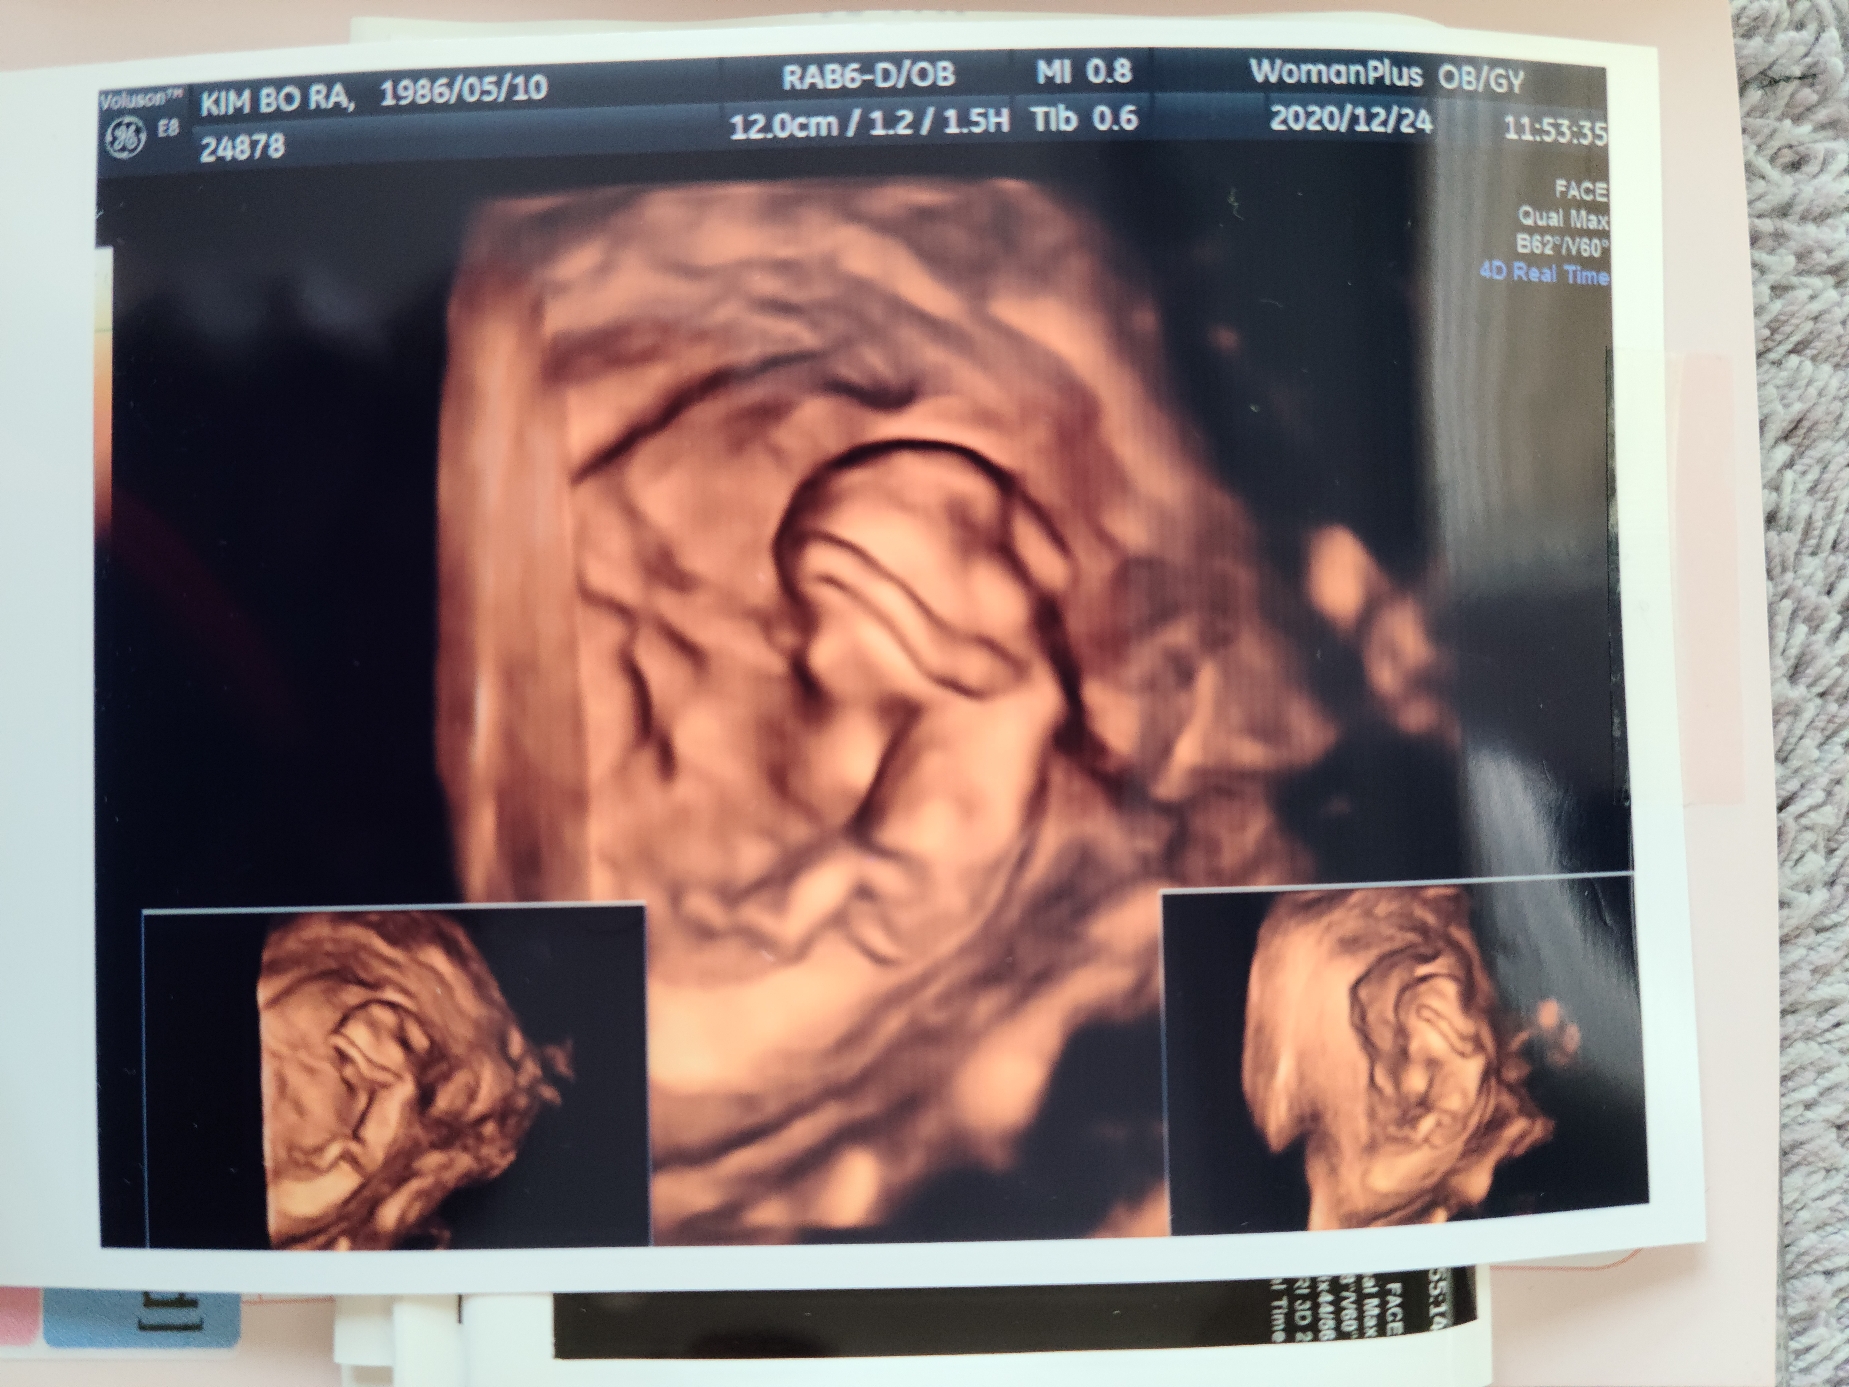

불안한 마음에 병원에 가서 검사한 결과 다행히 아무런 이상없이 건강하게 자라고 있음을 확인했어.

엄마 뱃속에서 뛰고 있는 무탈이 심장을 보며 아빠는 고마움과 기쁘이 남쳐 눈물이 고였다.